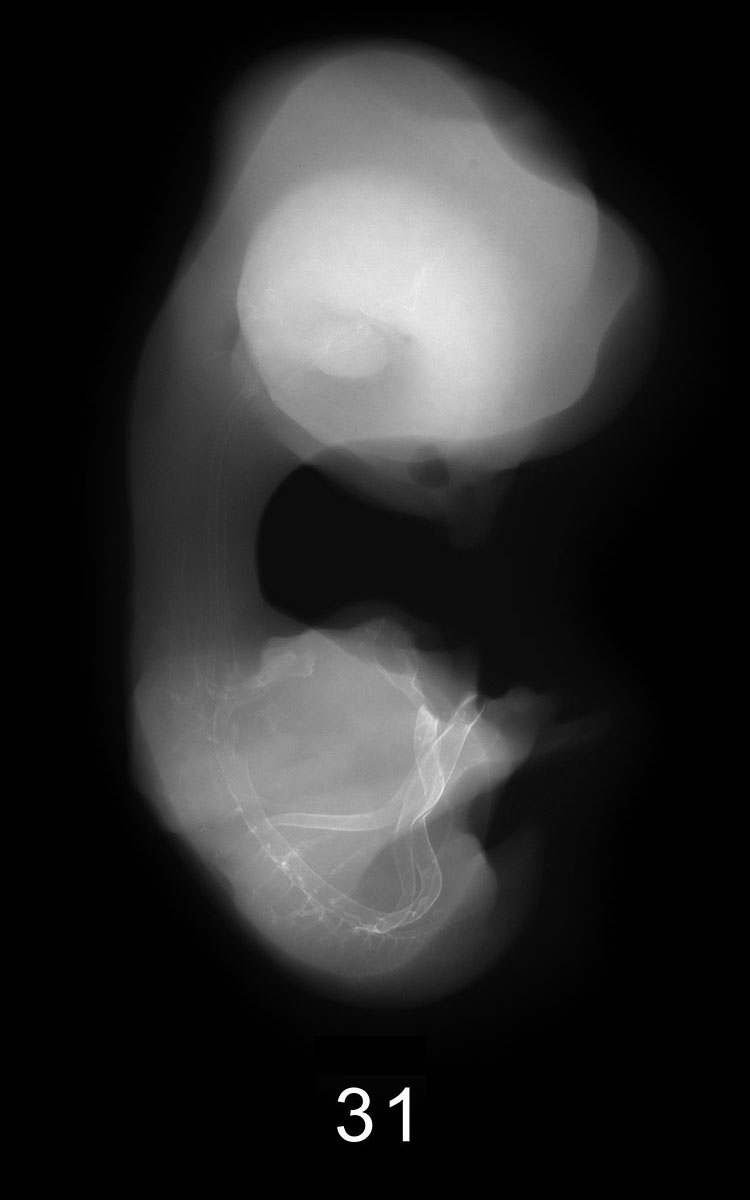

Chick Embryo Microangiography

Images listed by Hamburger-Hamilton (HH) Stage

Hamburger-Hamilton (HH) stages are a system used by those who study chick embryo development to describe the apparent maturity of the developing chick from laying of the egg to hatching. An embryo is assigned an HH stage (numbered from 1 to 46) based on its physical shape and visible features (morphology). This staging system is not dependent on the chronological age nor the size of the embryo, which are susceptible to variations due to breed, temperature during incubation, season, and time between egg laying and incubation. The stages, are in a sense, arbitrary levels of maturity based on multiple physical features. For example, embryos that might have different ages or sizes might be assigned the same HH stage based on their external appearance due to the natural variation which occurs between individuals or due to differing conditions during incubation.